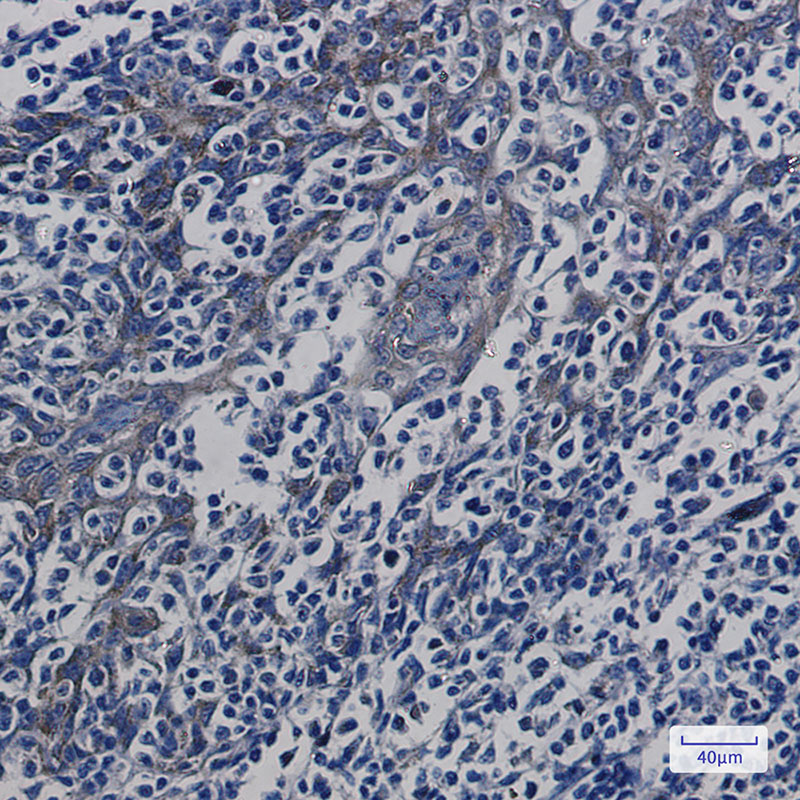

Product Image

IHC | 1/50-1/100 |